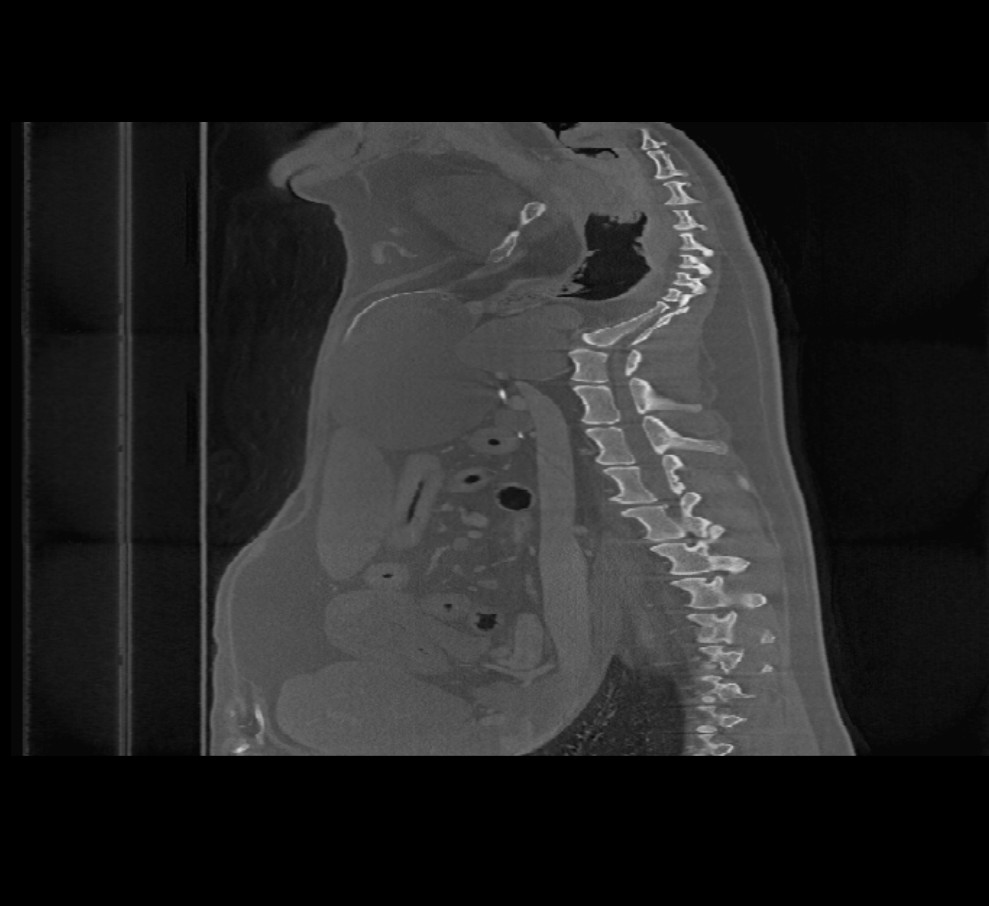

When opening volumetric DICOM images in the Viewer (CT and MR modality), an additional menu is available in the top toolbar titled Image Planes. Change the orientation of the image by choosing one of three available planes (Axial, Coronal,

and Sagittal).

The chosen plane affects the position and orientation of the CT/MR slices and their reconstruction on the 2D plane.